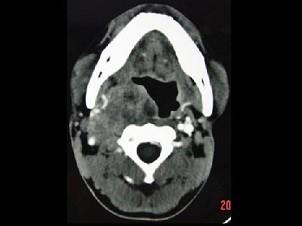

问题 男,41岁,右侧咽部不适两年余,有异物感,声音嘶哑,CT如图所示,最可能诊断为 ( )

选项 A、小唾液腺瘤 B、咽旁神经鞘膜瘤 C、咽旁转移癌 D、咽旁淋巴瘤 E、颈动脉体瘤

答案 B